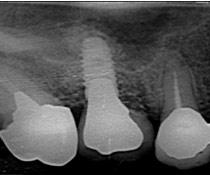

Yさんはバネがかかっている歯を守るために、インプラント治療を選びました。入れ歯の4本の部分にインプラントを入れたのでした。

Yさんはバネがかかっている歯を守るために、インプラント治療を選びました。入れ歯の4本の部分にインプラントを入れたのでした。

Bさんは数年前に左下の奥歯2本を抜きました。その時の先生は、インプラント治療をやっていなかったので、入れ歯を作りました。Bさんは入れ歯を入れてみて、その違和感にびっくりしました。結局Bさんは、ほとんど入れ歯を使うことなく、はずしたままで過ごしました。なぜなら、入れ歯がなくても反対側の歯で普通に食べることができたのです。Bさんは右側だけで、食べることにしました。

Bさんは数年前に左下の奥歯2本を抜きました。その時の先生は、インプラント治療をやっていなかったので、入れ歯を作りました。Bさんは入れ歯を入れてみて、その違和感にびっくりしました。結局Bさんは、ほとんど入れ歯を使うことなく、はずしたままで過ごしました。なぜなら、入れ歯がなくても反対側の歯で普通に食べることができたのです。Bさんは右側だけで、食べることにしました。

Bさんの右側だけでの食事が数年続いた時、異変がおこりました。右側だけの食事のせいで右の奥歯が悲鳴をあげたのです。Bさんは右の奥歯は1本失うことになりました。

Bさんの右側だけでの食事が数年続いた時、異変がおこりました。右側だけの食事のせいで右の奥歯が悲鳴をあげたのです。Bさんは右の奥歯は1本失うことになりました。

右に1本、左に2本のインプラントを入れ、Bさんは破壊の連鎖から抜け出すことができました。